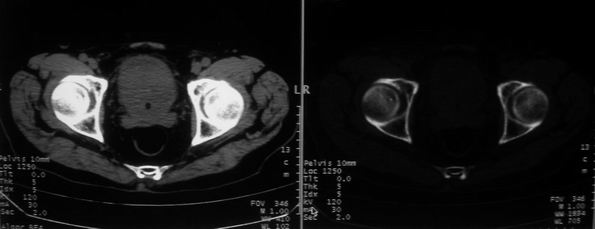

男,85岁,排尿困难。骶椎有问题吗?

前列腺明显增大,突入膀胱,各叶比例协调,密度均匀,精囊腺及精囊角正常;考虑良性增大。

骶骨没有看到明显异常。

1)前列腺明显增大,突入膀胱,各叶比例协调,密度均匀,精囊腺及精囊角正常;考虑前列腺增生症并阻塞性膀胱炎。2)骶椎右侧类似囊状骨质密度减低区,边缘骨质硬化,其内为软组织密度影填塞,相邻之骶椎椎管受压变形;考虑为骶椎右侧囊肿或神经纤维瘤。

建议:行mri检查。